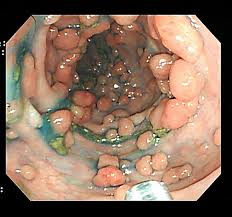

① 대장내시경 검사

가장 정확한 진단 방법은 대장내시경 검사입니다. 용종이 발견되면 절제 후 조직검사를 통해 암 여부를 확인할 수 있습니다.